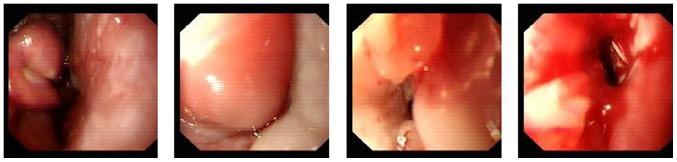

Primary esophageal natural killer (NK)/T-cell lymphoma is a markedly rare tumor. There were only 6 cases of the disease identified prior to June 2015. In the present study, the aforementioned cases were validated, and relevant computed tomography (CT) results and clinical features of primary esophageal NK/T-cell lymphoma were determined, to increase awareness of this type of tumor. CT features and clinical presentations of a patient with pathologically confirmed esophageal NK/T-cell lymphoma was analyzed. The patient exhibited non-specific clinical symptoms and CT images revealed diffuse thickening of the entire length of the esophagus. The patient received cycles of systemic chemotherapy and subsequent chest CT images demonstrated prompt and marked shrinkage of the tumor. At the time of writing, the patient has survived for 24 months and experiences a good quality of life without postprandial fullness or difficulty swallowing solid food. In addition, the characteristics of 6 patients with complete clinical features of this type of tumor, on the basis of a review of published studies (online PubMed, Medline, Google Scholar, Chinese Biomedicine Database and China Journal Full Text Database search), were retrospectively analyzed. Although primary esophageal NK/T-cell lymphoma is a markedly rare tumor, it is considered to be included in differential diagnosis of patients presenting with a fungal or viral infection, therapy-related mucositis or reflux esophagitis. The final diagnosis of primary esophageal NK/T-cell lymphoma is on the basis of a combination of clinical, CT and histopathological results.

原发性食管自然杀伤(NK)/T细胞淋巴瘤是一种极为罕见的肿瘤。在2015年6月之前仅确诊6例该疾病。在本研究中,对上述病例进行了验证,并确定了原发性食管NK/T细胞淋巴瘤的相关计算机断层扫描(CT)结果及临床特征,以提高对这类肿瘤的认识。分析了1例经病理证实的食管NK/T细胞淋巴瘤患者的CT特征及临床表现。该患者表现出非特异性临床症状,CT图像显示食管全长弥漫性增厚。患者接受了多周期全身化疗,随后的胸部CT图像显示肿瘤迅速且显著缩小。在撰写本文时,该患者已存活24个月,生活质量良好,无餐后饱胀感或吞咽固体食物困难。此外,在回顾已发表研究(通过在线检索PubMed、Medline、谷歌学术、中国生物医学数据库和中国期刊全文数据库)的基础上,对6例具有这类肿瘤完整临床特征的患者的特点进行了回顾性分析。虽然原发性食管NK/T细胞淋巴瘤是一种极为罕见的肿瘤,但在对表现为真菌或病毒感染、治疗相关的黏膜炎或反流性食管炎的患者进行鉴别诊断时应考虑该病。原发性食管NK/T细胞淋巴瘤的最终诊断基于临床、CT及组织病理学结果的综合判断。